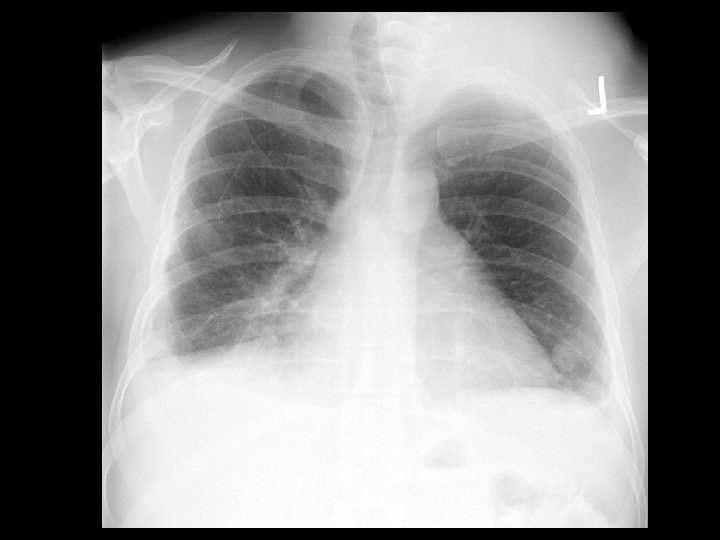

Type A aortic dissection • Findings: – Bilateral pleural effusions – CT is diagnostic • ddx: – NONE! – This is an Aunt Minnie!